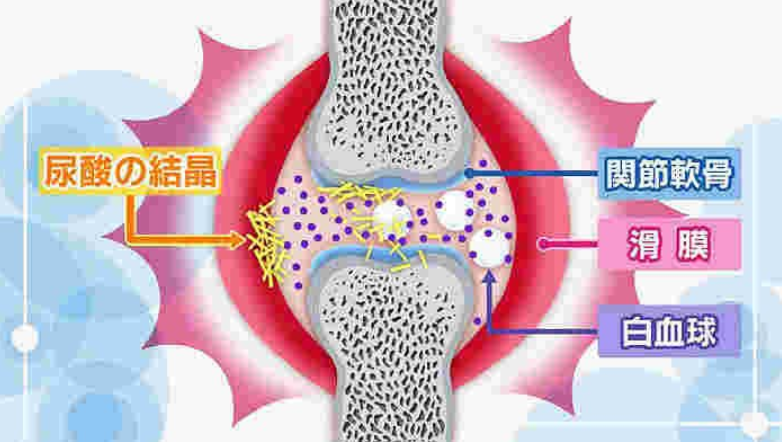

痛風は尿酸が体の中にたまり、それが結晶になって激しい関節炎を伴う症状になる病気です。医学研究が進み、良い薬も開発されたため正しい治療を受ければ全く健康な生活が送れます。しかし、放置すると激しい関節の痛みを繰り返したり、体のあちこちに結節が出来たり、腎臓が悪くなったりする重大な病気でもあります。

痛風の原因はプリン体の過剰摂取で、ビールやたらこなどのプリン体の含有量が多い食べ物を過度に体内に取り込む事で、尿酸が関節に沈着し、尿酸値が高くなることで痛風関節炎は頻発します。

症状が進行すると、高尿酸血症に伴う臓器障害(尿路結石、痛風腎)なども生じてしまいます。